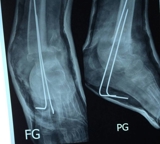

Re-dislocatie van stabiele distale fractura antebrachii bij kinderen: het herstel vermogen van een kind is natuurlijke innovatie

L.W. Diederix, K.C. Roth, P. Edomskis, L.U. Biter, M.R. de Vries, J.H. Allema, R.M.H. Wijnen, G.A. Kraan, M. Reijman, J. A. N. Verhaar, J. W. Colaris